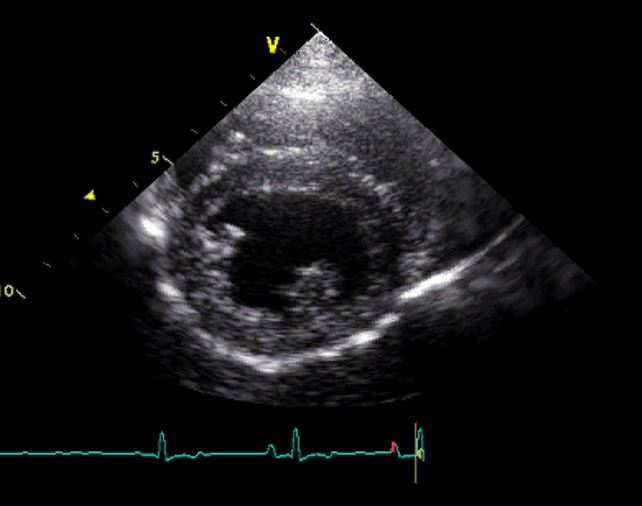

Q

Which view is this?

A

Right parasternal short axis @ mitral valve